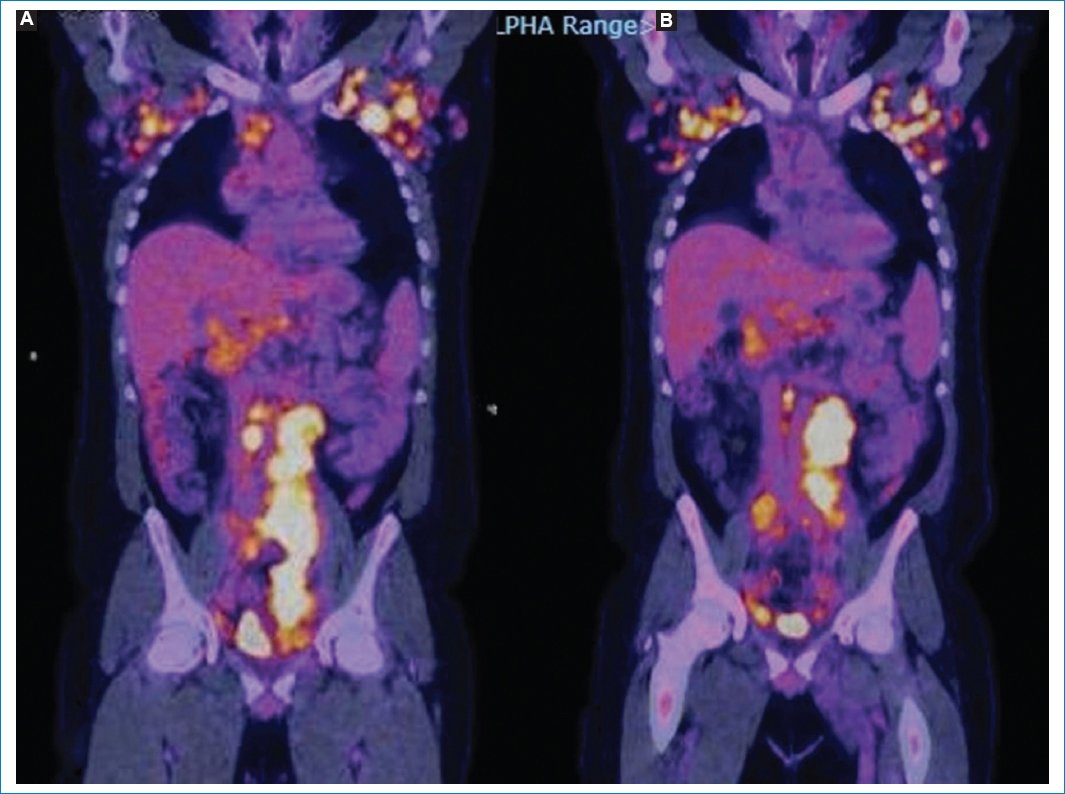

Figura 10. Mujer de 49 años con diagnóstico de linfoma no Hodgkin agresivo (misma paciente de la figura 4), con progresión de su enfermedad y de la LP, con actual compromiso difuso del peritoneo (flecha roja), adenomegalias múltiples hipermetabólicas en diferentes niveles ganglionares (flecha azul) y compromiso óseo (flecha verde); hallazgos evidentes en los cortes coronales de TC (A), fusión PET-TC (B) y MIP (C y D).

Figura 11. Varón de 66 años con diagnóstico de linfoma difuso de células B grandes y LP. Imágenes axiales de TC (A), MIP (B) y fusión PET-TC (C) que evidencian compromiso peritoneal difuso con aumento de consumo de 18F-FDG (flecha). Nótense, asimismo, las adenomegalias hipermetabólicas y las masas peritoneales acompañando el proceso difuso.